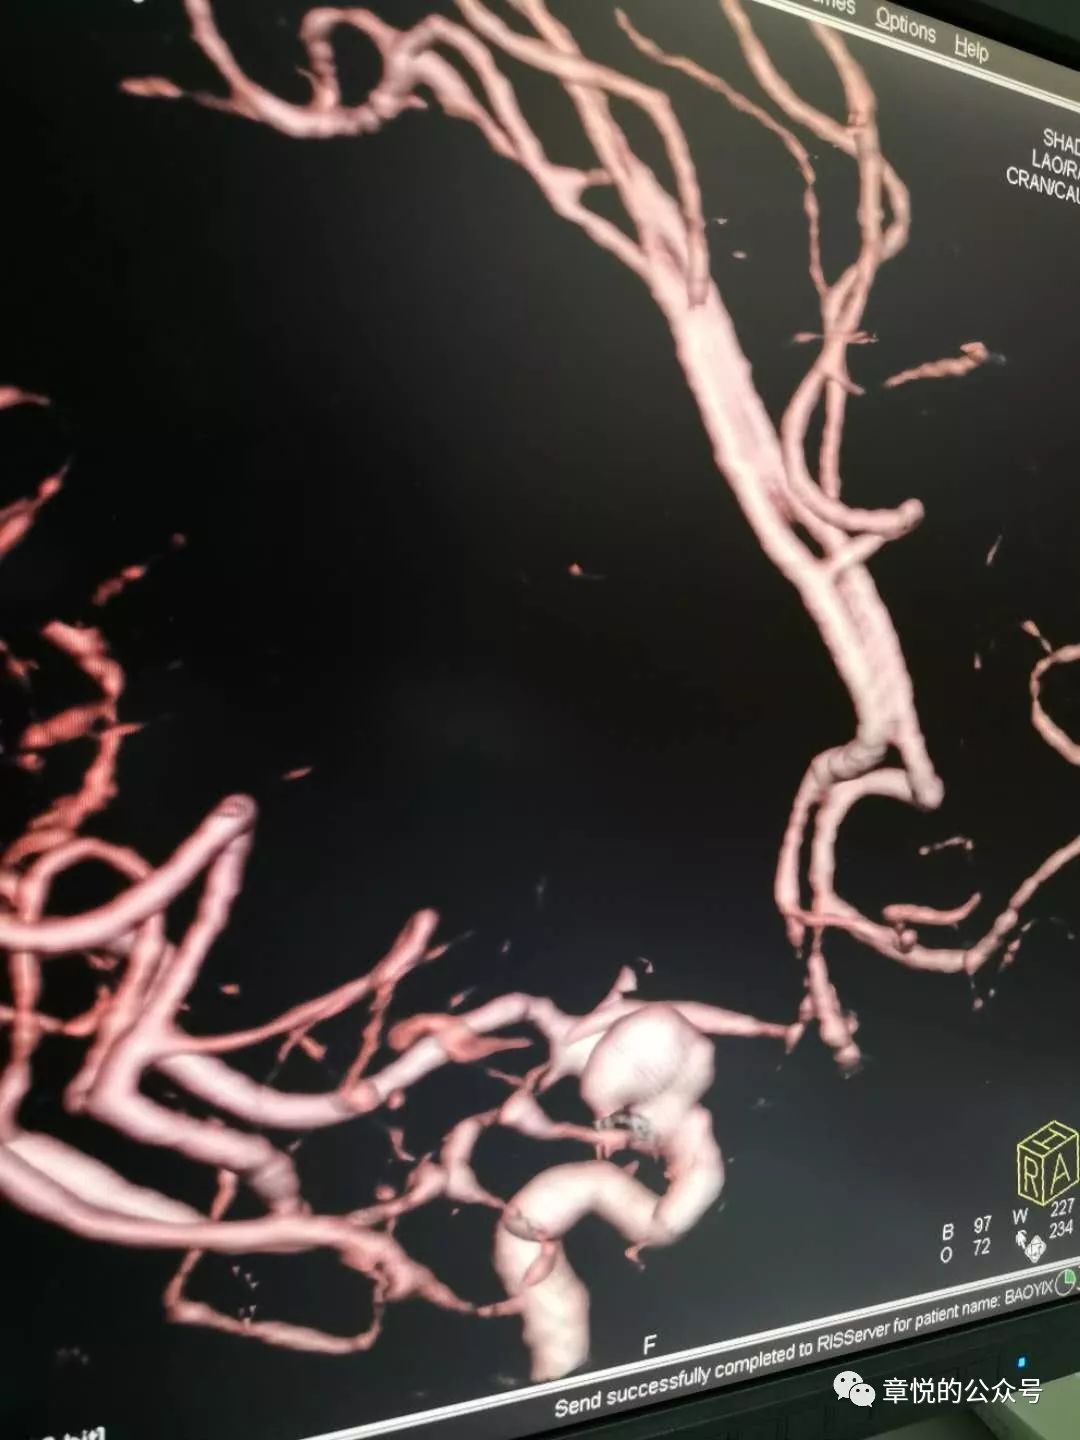

当时我科病房床位爆满,所以我建议到附近的八五医院就诊,到了那里很快就收入院,当天下午就出了结果,答案是动脉瘤(图1)。腰穿放出来全是血性液体,即蛛网膜下腔出血。

图1. 左侧颈内动脉未见显影,右侧颈内动脉远端见动脉瘤,并伴有多根血管狭窄